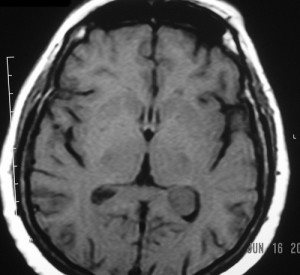

The images are a combination of T1 (before and after gadolinium enhancement), T2, and FLAIR pulse sequences in axial, sagittal and coronal sections of the patient’s brain (not all of the original images are in the monograph).

They reveal a 2cm mass in the trigone of the left lateral ventricle, centered within the choroid plexus. It has intermediate signal intensity on the pre-gadolinium T1WI, is hyperintense on the T2WI and enhances intensely and homogeneously after intravenous gadolinium administration. The mass is round, well-defined, has no mass-effects and does not invade the brain parenchyma. The ventricles are not dilated. The remainder of the brain is normal.